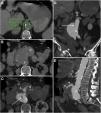

Fístula ilioentérica secundaria en un varón de 93 años, con antecedente de bypass aortobifemoral, que acude por presentar vómitos en posos de café y melenas. No se administra contraste intravenoso por disminución de la tasa de filtrado glomerular. Se representan cortes craneocaudales en el plano axial (A, B, C) del bypass aortobifemoral (punta de flecha) localizado en una disposición anterior a la aorta nativa (a). En la figura C se identifica gas intraluminal en la rama derecha del bypass (flecha) procedente del asa intestinal inmediatamente adyacente; se indica la arteria ilíaca nativa como referencia anatómica (i). La reconstrucción sagital (D) representa el nivel de los cortes.

Fístula aortoentérica secundaria en varón de 78 años con antecedente de bypass aortobifemoral y enfermedad ulcerosa péptica que acude por cuadro de hemorragia digestiva alta. La endoscopia reveló una ulceración de la pared intestinal con observación directa del material del bypass. Ante la estabilidad hemodinámica del paciente se decide valorar con tomografía computarizada. Fases arterial (A), portal (B) y reconstrucción MIP en el plano sagital (C). El bypass aortobifemoral se observa en íntimo contacto con el duodeno retroperitoneal presentando un manguito de partes blandas que rodea el bypass (*) y una burbuja de aire ectópico (punta de flecha) sin plano graso de separación. Aunque no se demuestra extravasación activa de CIV, la cirugía confirmó la presencia de FAE.

Fístula aortoesofágica primaria en varón de 67 años con hematemesis, sudoración profusa, palidez cutánea e hipotensión. La tomografía computarizada basal (A) muestra una dilatación esofágica con contenido intraluminal de alta atenuación en relación con componente hemático (*) y desplazamiento de calcificaciones intimales que indica rotura de placa ateromatosa con puerta de entrada (flecha). La fase arterial en plano axial (B), reconstrucción sagital (C) y volumétrica (D) muestra calcificaciones en la pared de la aorta descendente y una dilatación sacular (punta de flecha) que contacta con la pared esofágica sin plano graso de separación. Estos hallazgos sugieren úlcera penetrante. A pesar de la ausencia de extravasación de contraste intravenoso, se confirmó la presencia de fístula aortoentérica en la cirugía.

Fístula aortoduodenal primaria en varón de 65 años con episodio de vómitos intermitentes y melenas de 2 semanas de evolución que acude a Urgencias con hematemesis, mareo e hipotensión. La tomografía computarizada basal (A, B) demuestra contenido de alta densidad (47 UH) en la cámara gástrica en relación con coágulo y un aneurisma calcificado en aorta abdominal con hematoma intramural. La fase arterial (C) revela un abombamiento sacular en la cara anterolateral de la aorta con pérdida del plano graso de separación con el duodeno (*). En fase tardía (D) no se demuestra clara extravasación de CIV. La laparoscopia confirmó la presencia de FAE (E) (a: aorta; d: duodeno; f: fístula) que fue reparada en el mismo acto quirúrgico (F) incluyendo resección segmentaria del duodeno.